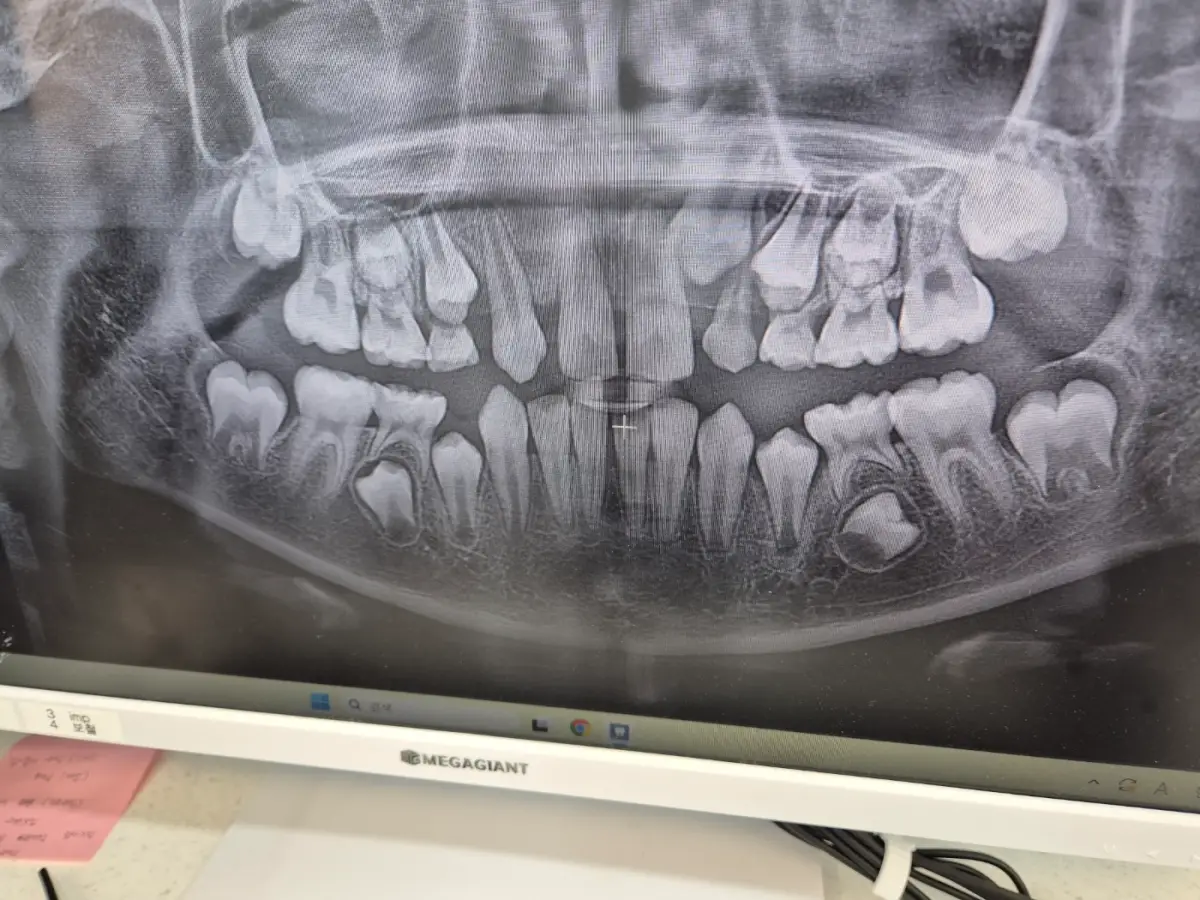

초5학년 아이가 저녁에 치아가 흔들려서 아프다고 해서 바로 예약을 하고 진료를 받았습니다.

첫째가 지금 교정치과를 다니고 있어 혹시나 하는 불안감이 있었지만 괜찮겠지.. 하면서 발치만 하면 되겠지 하는 마음으로 방문헤서 엑스레이 촬영을 하고 기다리는 순간... 두둥~~~!!!!!!!!

발치를 하러 갔는데 충치치료 그리고 대학병원추천까지

처음 진료를 받으러 가시면 엑스레이 촬영하게 되는데요.

아이의 아래치아가.... 옆으로 자라고 있었습니다.

오른쪽 아랫이 보시면 완전 누워서 자라고 있는 치아입니다.

어금니를 밀어 통증이 올 수 있으니 가능하면 빨리 진료를 받으시는 게 좋은 것 같다고 이야기해 주셨습니다.

저는 발치때문에 자주 집 근처 치과를 방문하게 되었는데 이런 소식을 듣게 되어서 조금 놀랐지만 치료를 하면 되는 것을 알고 있었고 경험도 있어서 아이도 크게 걱정하지 않을 수 있었습니다.